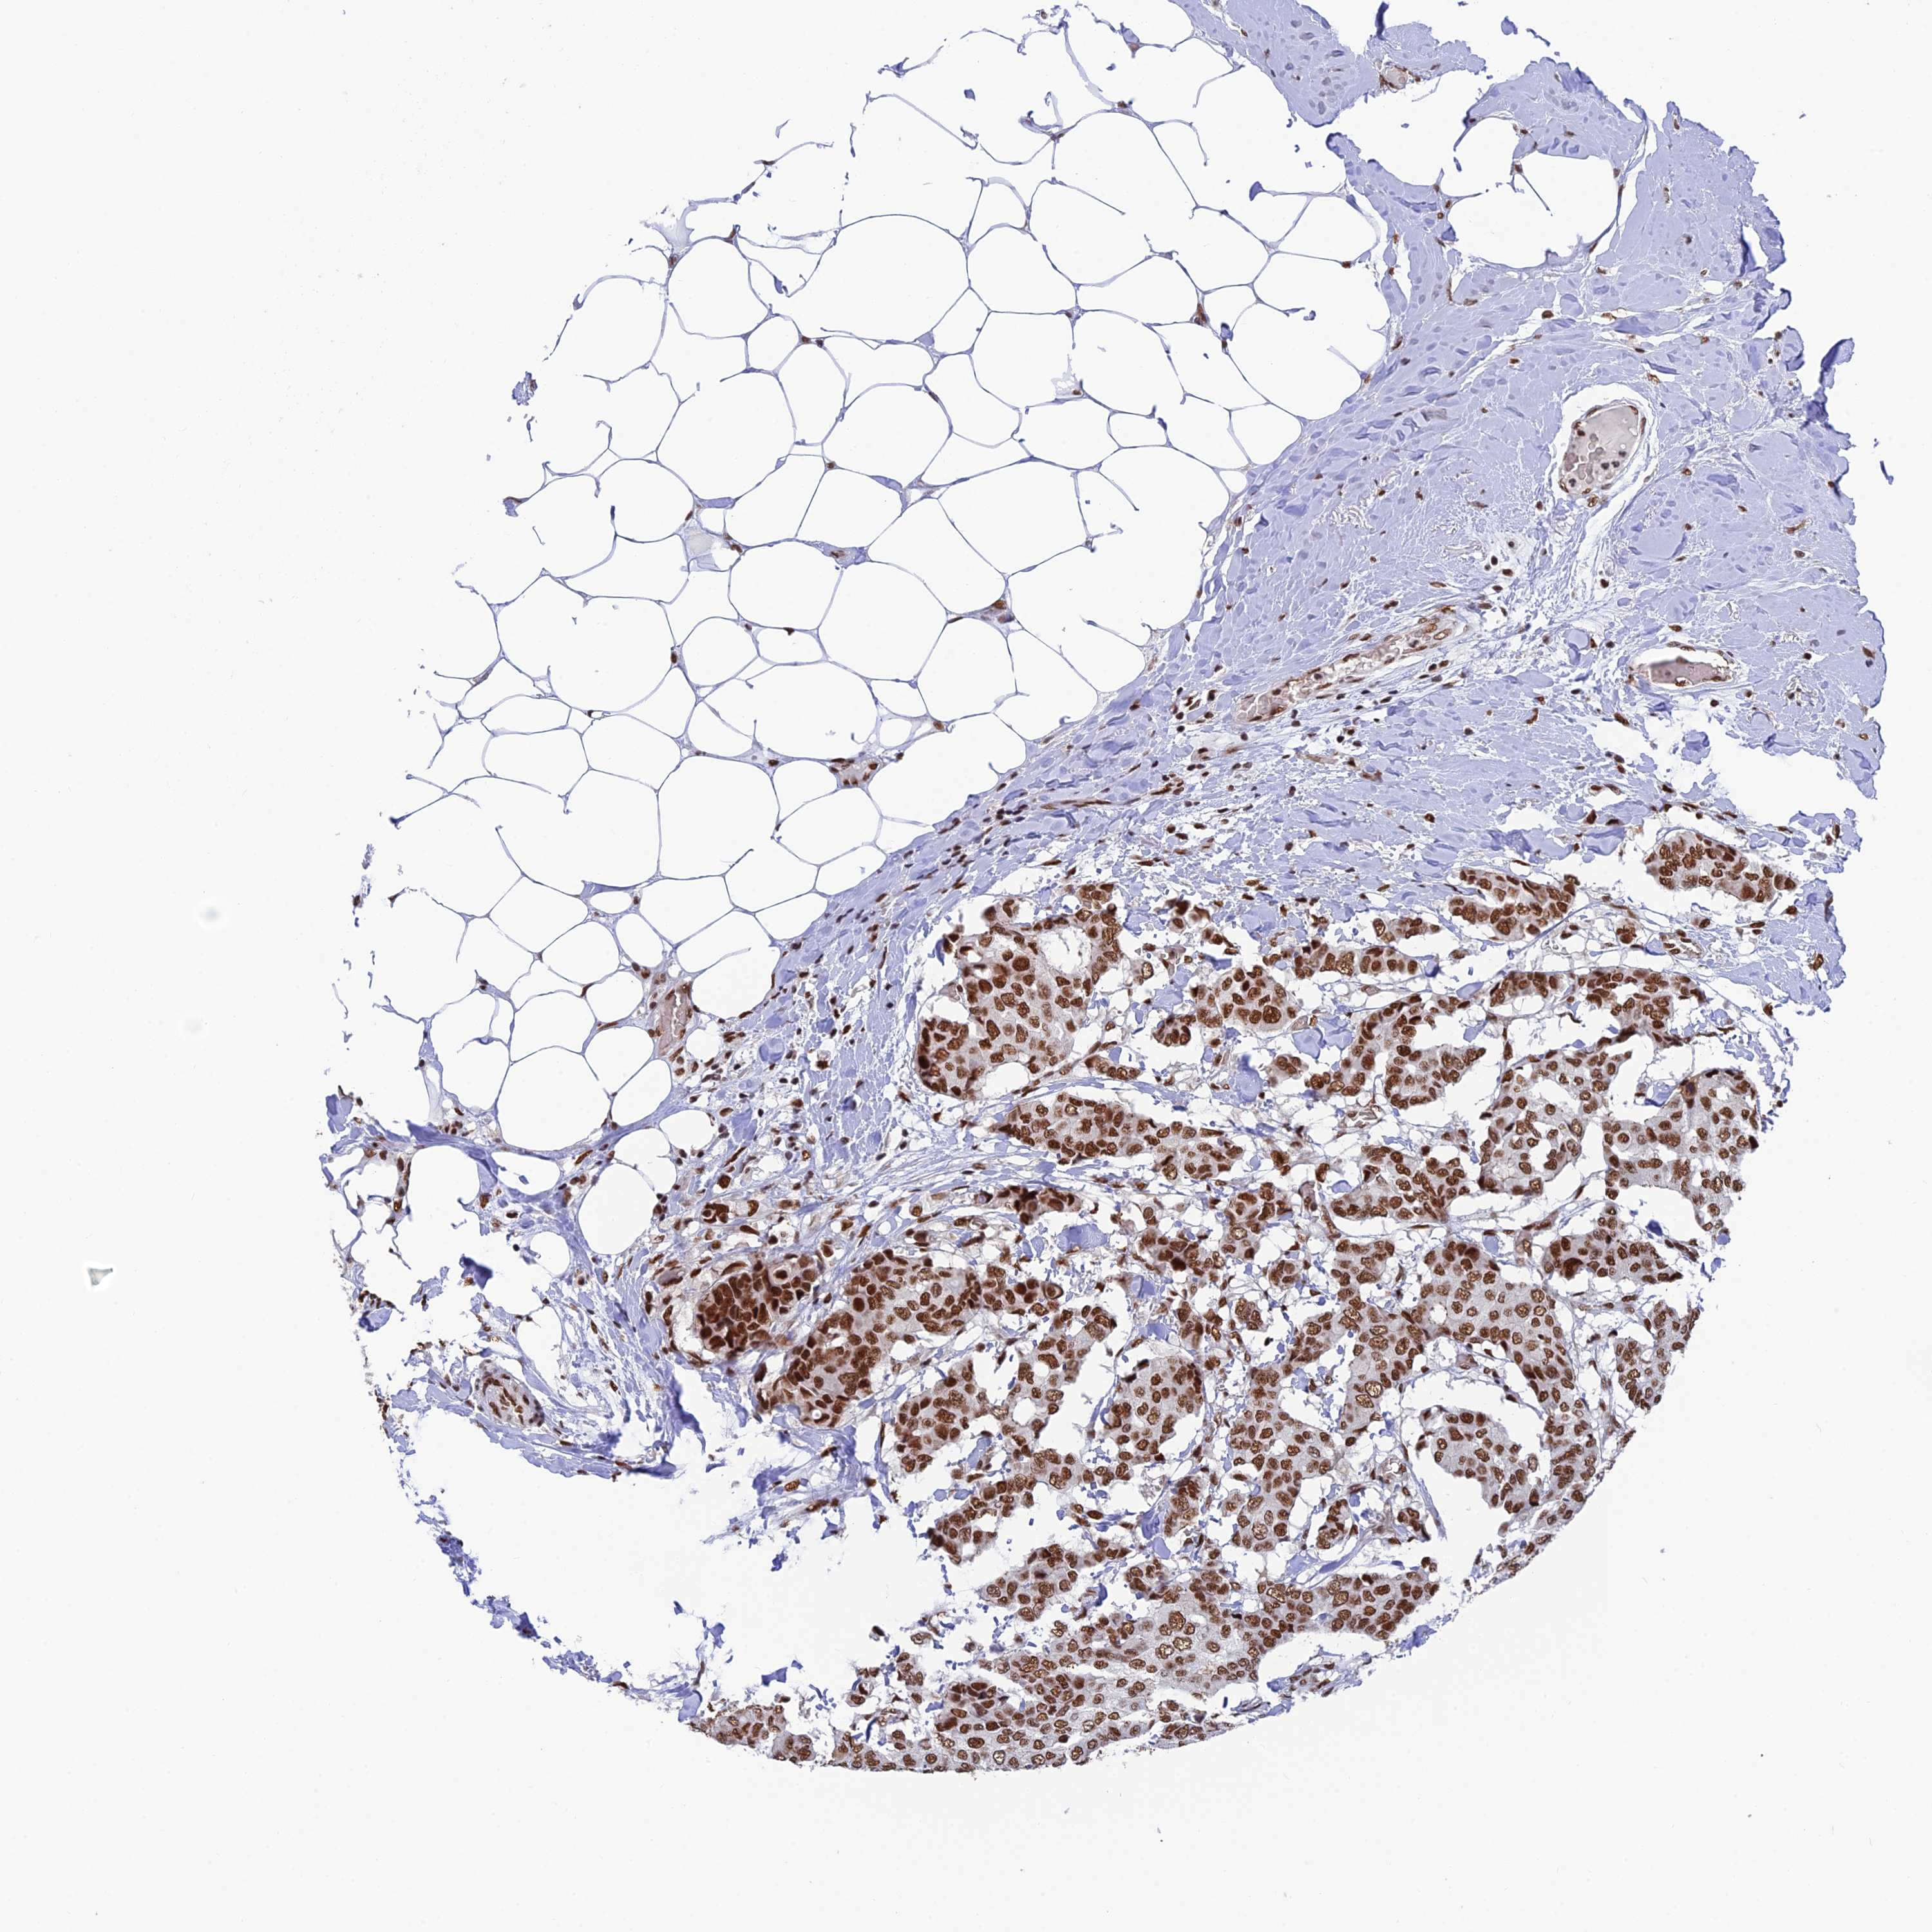

BRCA TCGA BRCA VALIDATION PROTEIN EXPRESSION